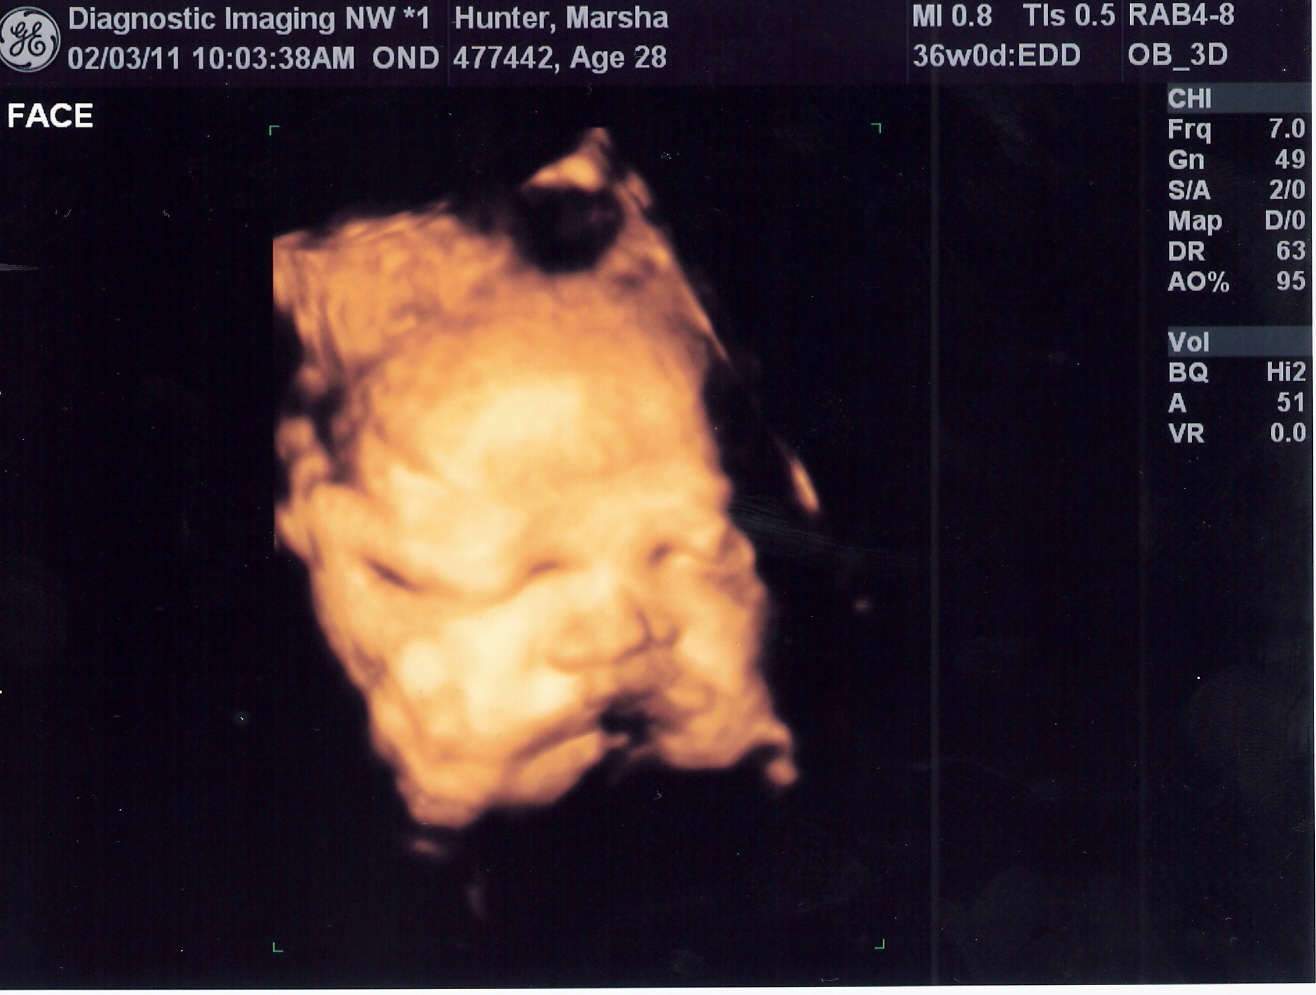

Had an ultrasound today to check the progress of this little guy. Everything is on target and his estimated weight at this point is 5 lbs. and 12 oz. and due date based on his growth is March 3rd!

3d of his chubby cheeks,

so kissable already

resting his head on his forearm, if you look closely you can see his

fingers :-)